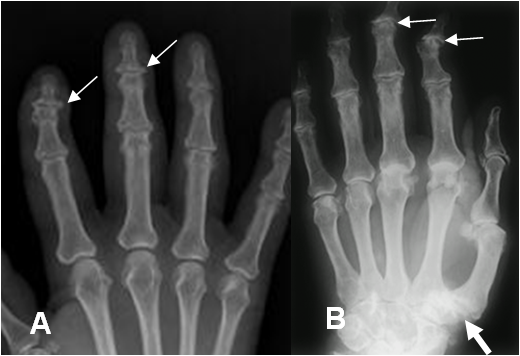

Fig 11. Artropatía degenerativa.

A y B: Rx AP. Cambios degenerativos de predominio distal (Flechas delgadas) y en la 1º articulación metacarpofalángica. (Flecha gruesa).